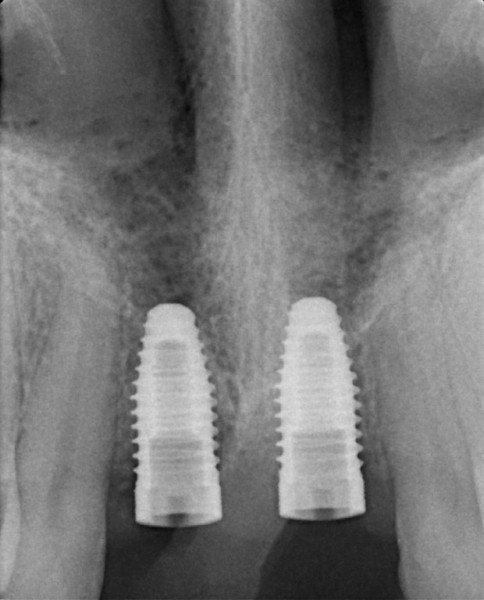

A Case with a Fractured Central Incisor